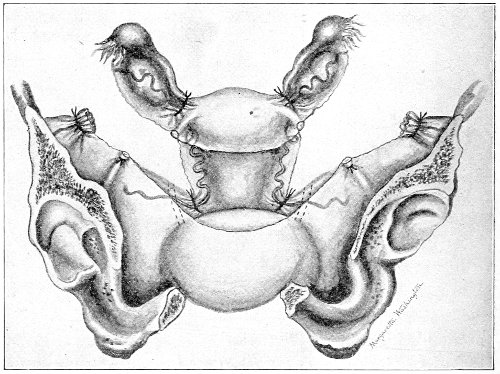

The injuries to the perineum that may result from childbirth are classified according to the position or the direction and extent of the laceration. They are as follows: slight median tear; median tear involving the sphincter ani; tear in one or both of the vaginal sulci; subcutaneous laceration of the muscles and fascia.

All these injuries demand operative treatment. The operation for the repair of injuries to the perineum is called perineorrhaphy. It is called immediate or primary, intermediate, and secondary perineorrhaphy, according to the time after the receipt of the injury at which the operation is performed. The primary operation is done during the first twenty-four hours. The primary operation should always be performed. A careful inspection of the perineum and the posterior vaginal wall should always be made after labor, and any laceration should be repaired within twenty-four hours. The advantages of the primary operation are many. The parts are usually so numb that it is not necessary to administer an anesthetic. No denudation is necessary, and therefore no tissue need be sacrificed. The woman is spared the pain and discomfort of granulation and cicatrization.

The bad results that follow neglect of the primary operation are very numerous, and will be studied hereafter. The injured muscles retract, and, being functionally useless, undergo atrophy, and when finally repaired never possess their former strength. Involution in the vagina and the uterus may be arrested, and all the disasters incident to subinvolution may appear. Vaginal and uterine prolapse occur; the natural supports of the 63 vagina and uterus become stretched, and, though afterward the perineum may be restored, yet it may be found impossible to retain the uterus in its proper position. It is always good surgery to repair an injury as soon as possible.

When practicable, a certain amount of preparation of the patient should be made before the operation of perineorrhaphy. This is most easily effected before the intermediate and secondary operations. The vagina and the vulva should be sterilized, and the intestinal tract should be emptied. Thorough evacuation of the bowels is most important when the sphincter ani has been injured, because it is desirable, after operation for this lesion, that the bowels should not be moved for five or six days. A saline purgative should be administered on an empty stomach about five hours before the operation, and a rectal injection of soap and water should be administered about one hour before the operation. Whatever purgative be employed, it should be administered at such a time that its action shall have ceased by the time of the operation. If this precaution is not observed, there may be a discharge of feces that will infect the wound and interfere with the manipulations.

For operation upon the perineum the woman should be placed in the dorso-sacral position (Fig. 1, page 23).

The intermediate operation is performed during the granulation period—ten days or two weeks after labor. At this time the raw surfaces are covered with granulation-tissue and bathed with pus. The edges of the wound and the surrounding tissue may be hard and swollen from infiltration with inflammatory products. In the intermediate operation it is necessary to administer an anesthetic or to anesthetize the parts locally with a 10 per cent. solution of cocaine.

All cicatricial tissue, granulation-tissue, and rough edges should be scraped away with the knife, the scissors, or the curet. The raw surfaces should be thoroughly 64 washed with a 50 per cent. solution of peroxide of hydrogen and a 1:1000 solution of bichloride of mercury. The sutures should then be introduced.

The secondary operation is performed at any time after cicatrization has occurred—often many years after the receipt of the injury. This operation is at present one of the commonest in gynecology, because the injury is not detected, is neglected, or is improperly repaired after labor. In the secondary operation an anesthetic is necessary. The mucous membrane must be removed or denuded on the posterior wall and about the mouth of the vagina, in order that the lacerated structures may be brought again in apposition. The denudation is best made by means of scissors curved on the flat (Figs. 24 and 25).

The strip of mucous membrane to be removed is picked up with a tenaculum (Fig. 26) or with tissue forceps 65 (Fig. 27); the scissors are placed with the blades parallel to the surface to be denuded, and the strip is cut away evenly, in one piece if possible. A similar contiguous strip is removed, and so on until the necessary surface is bare. Sponges in holders (Fig. 28) or continuous irrigation may be used to remove blood.

The sutures may be fastened by passing the ends through a perforated shot which is slipped down to the line of union and compressed by the shot-compressor (Fig. 32). All blood should be carefully removed from the surfaces that are brought together. The sutures should only be sufficiently tense to produce accurate apposition. A light gauze drain should be introduced in the vagina, and should be removed in forty-eight hours. Afterward one vaginal douche of about a quart of warm bichloride solution (1:2000) should be administered every day. After the douche the labia should be separated and the vagina carefully dried by cotton held in dressing-forceps. Except in those cases in which the sphincter ani is involved, the bowels may be moved on the second or third day. The woman should stay in bed for two weeks, at the end of which time the sutures should be removed. 67 She should avoid heavy lifting, long standing, and bicycle- or horseback-riding for two months after the operation. Constipation should always be avoided. Coitus may be resumed six weeks after operation.

Slight Median laceration of the Perineum.—In this injury the tear takes place through the fourchette. Posteriorly it may extend as far as the sphincter ani muscle. Upward it may extend for an inch up the posterior vaginal wall. The appearance of this tear is shown in Fig. 33. It will be noted that, as this tear takes place in the median line, none of the muscles that support the perineum are involved, nor are the planes of fascia injured. The perineum is slightly split, and the insertions and origins of the muscles and the fascia are slightly separated. The supporting structures of the perineum and the pelvic floor are, however, uninjured.

Fig. 33.—Recent slight median laceration of the perineum: sutures introduced.

If this tear is detected after labor, it should be closed by the immediate operation. A slight tear involving chiefly the cutaneous aspect of the perineum should be closed by three or four sutures introduced from the outside, as in Fig. 33. The needle should be introduced about a quarter of an inch from the edge of the wound. It should not be passed parallel with the plane of the lacerated surface, but should be swept outward and then inward toward the 68 angle at the bottom of the tear (Fig. 34). It may either emerge at the angle and be re-introduced, or it may be passed directly through to the skin-margin on the opposite side of the wound. If the suture is passed in this way, there will be perfect apposition throughout the whole surface of laceration. If the sutures are improperly passed, there may result only apposition of the skin-edges.

Fig. 34.—Diagram representing the correct and the incorrect method of passing the suture for closure of slight perineal laceration.

If the laceration extends up the posterior vaginal wall, two sets of sutures must be introduced—one on the vaginal aspect of the tear, and one on the skin aspect (Fig. 35).